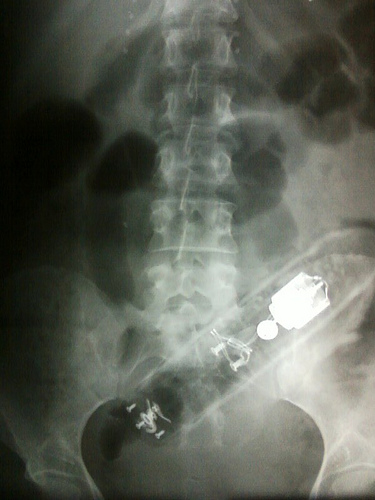

Recto

- Un corcho de vino envuelto en papel de cocina y cinta aislante, todo ello dentro de un condón.

- Una linterna

- Según la esposa del paciente, este último se sentó sobre un destornillador y se le subió hasta el recto.

- Un vaso de chupito

- Un cepillo para el pelo, el cual utilizaba para masturbase mientras su novio miraba, lo que le produjo una fisura rectal.

- Un cortador de las cutículas de las uña

- Un picahielo con el que intentaba empujar hacia dentro las hemorroides

- El mango de la escobilla del baño

- Un martillo

- Un rotulador de bingo

- Un bolo de Bowling

- Un consolador de 15 centímetros, el cual pertenecía a su esposa

- El palo de una escoba

- Una pelota de béisbol